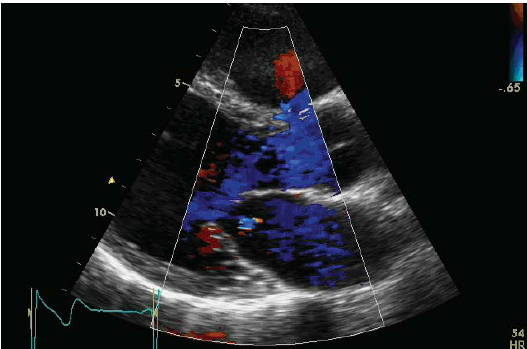

One of the primary calculations which veterinary cardiologists make when gathering data during echocardiographic (echo) scans of dogs' hearts is the LA/Ao ratio (LA ÷ Ao). "LA" stands for the left atrium of the heart, and in this context it is the linear diameter of the left atrium in either millimeters (mm.) or centimeters (cm.). "Ao" stands for the aortic root of the heart, and that is the linear diameter of the aorta artery at its starting point in the left ventricle of the heart, similarly in millimeters or centimeters.

The left atrium (LA) is one of the two chambers of the dog's heart (the

other being the left ventricle) which

enlarge as MVD progresses from just a soft murmur to congestive heart failure

(CHF). If in consecutive echo examinations of the same patient, the

cardiologist finds that the diameter of the LA has increased significantly,

that indicates that the MVD has progressed and the need to medicate the dog

with pimobendan. So, comparing the diameter of the LA in consecutive echo

scans is extremely important information in terms of treating the patient.

However, the aortic root (Ao) of the heart plays no role whatsoever in the progression of MVD. And, most significantly, the diameter of the Ao is not a constant number. It can change so that in one echo scan the Ao's diameter can be x and in a later scan it can be y. Indeed, the condition of the aortic root has been known to change as the dog ages; it deteriorates. So, the size of the Ao when measured when the dog is 5 years old may not be the same as it is when the same dog is examined at age 6 years. In short, it makes no sense to include the Ao measurement in calculations of changes in the dimension of the LA of a single dog.

A dilemma which veterinary cardiologists face when performing an initial echo scan of the heart of a MVD-affected dog is how to determine upon that initial scan whether the LA still is of normal size or already has begun to enlarge. Researchers attempt to resolve that difficulty by predicting the size of normal-sized LAs. The LA/Ao ratio was devised by medical researchers in a 1974 study of humans, based upon the assumption that humans' normal sized LAs and Aos are proportional to each other, and so the LA/Ao ratio can indicate a reference range of normal sized human left atriums and degrees of left atrial enlargement. If a patient's heart had never been echo scanned prior to suspected left atrial enlargement, the LA/Ao reference range can be used as a best guess as to whether any enlargement already has occurred.

Ignoring the fact that there is a far vaster array of body types, heart sizes, and artificially selected breeds among canines than there are among humans, veterinary researchers nevertheless adopted the LA/Ao ratio and have used it in their research studies to determine reference ranges for normal sized canine hearts. If they have, say, 50 dogs in their study, and they want to compare progression of MVD in the LAs of all of those dogs, they contend that using reference ranges based upon the LA/Ao ratio, instead of just each dog's LA measurement alone, enables the researchers to detect and calculate any cardiomegaly (heart enlargement) among the dogs in the study. (That contention is totally fictitious on a species-wide basis, by the way, but that discussion will be left for another part of this series.) Intellectual laziness fits handily here. For example, in the 2016 EPIC Study (which led to the conclusion that pimobendan should be used to treat MVD-affected dogs with enlarged hearts but not yet in CHF), its lead investigators made the totally unfounded assumption that all dogs (regardless of breed or size) with LA/Ao ratios less than 1.6 have normal sized LAs, and all dogs with LA/Ao ratios of 1.6 and above have enlarged LAs. Three years later, that nonsense was incorporated into the 2019 re-definition of Stage B2 of MVD in the ACVIM's 2019 Consensus Statement.

That said, the LA/Ao clearly has no useful role whatsoever when examining only a single dog's heart to determine if that dog's LA has enlarged between two consecutive echo exams. Since the Ao's diameter can be different in different echo scans of the same dog, when the Ao is included in an effort to determine if only the LA has increased in size, the result completely falsifies the diagnosis. Only if the Ao diameter is constant for all echo scans of that dog -- a very unlikely event -- will the LA/Ao ratio provide any useful information about the size of the dog's LA.